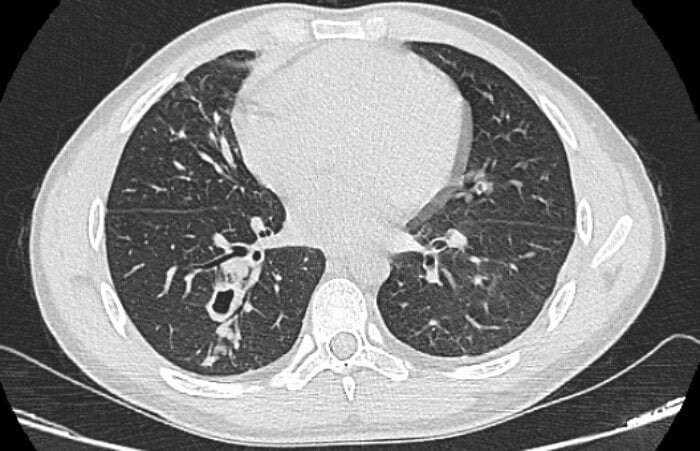

Ho ra máu, đi khám phát hiện sán làm tổ trong phổi

Một năm nay, nam thanh niên mệt mỏi, ho nhiều và ra máu, bác sĩ khám và chẩn đoán nhiễm sán lá phổi.